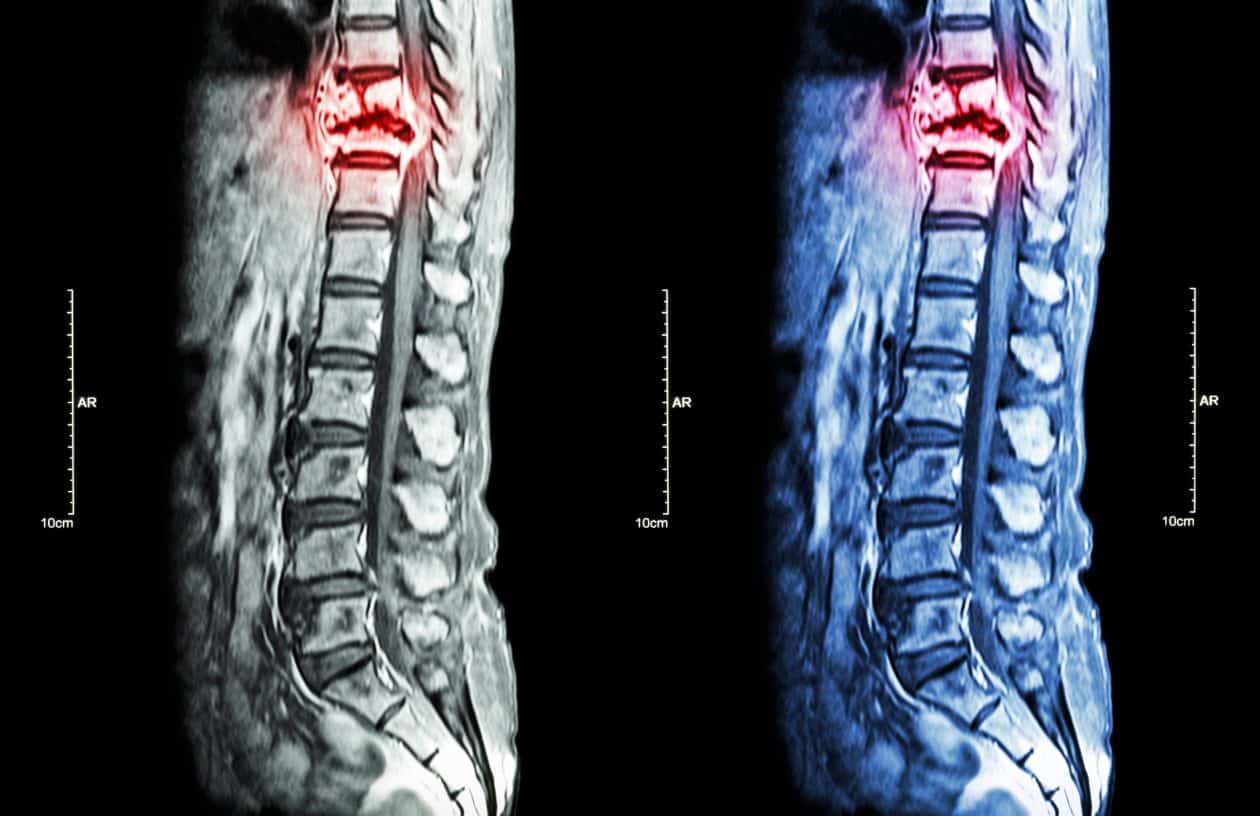

Entender el papel de la médula espinal, aclara la importancia de esta porción del sistema nervioso para el funcionamiento del cuerpo humano. Las lesiones de la médula espinal están relacionadas con la pérdida del movimiento de las extremidades y del control de los esfínteres, cambios en el tono muscular, reflejos o en la sensibilidad, entre otros problemas. Todos estos cambios están directamente relacionados con la altura de la lesión y el tamaño del daño causado a la estructura de la médula.

La lesión de la médula espinal, como su nombre indica, pueden ocurrir cuando hay daño en las células dentro de la médula espinal o cuando los nervios que la recorren están lesionados. La mayoría de las lesiones de la médula espinal son el resultado de accidentes automovilísticos, caídas, agresiones y traumatismos. Los síntomas como pérdida de sensibilidad, pérdida de fuerza muscular y pérdida de la función intestinal y vesical pueden ser temporales o permanentes. Si se lesiona la columna, la persona suele sentir dolor en la parte afectada del cuello o la espalda.

La lesión de la médula espinal es una emergencia médica que requiere tratamiento inmediato para reducir los efectos a largo plazo. El tiempo que se tarda en iniciar el tratamiento después de que se ha producido afecta directamente al resultado y eficacia del tratamiento.